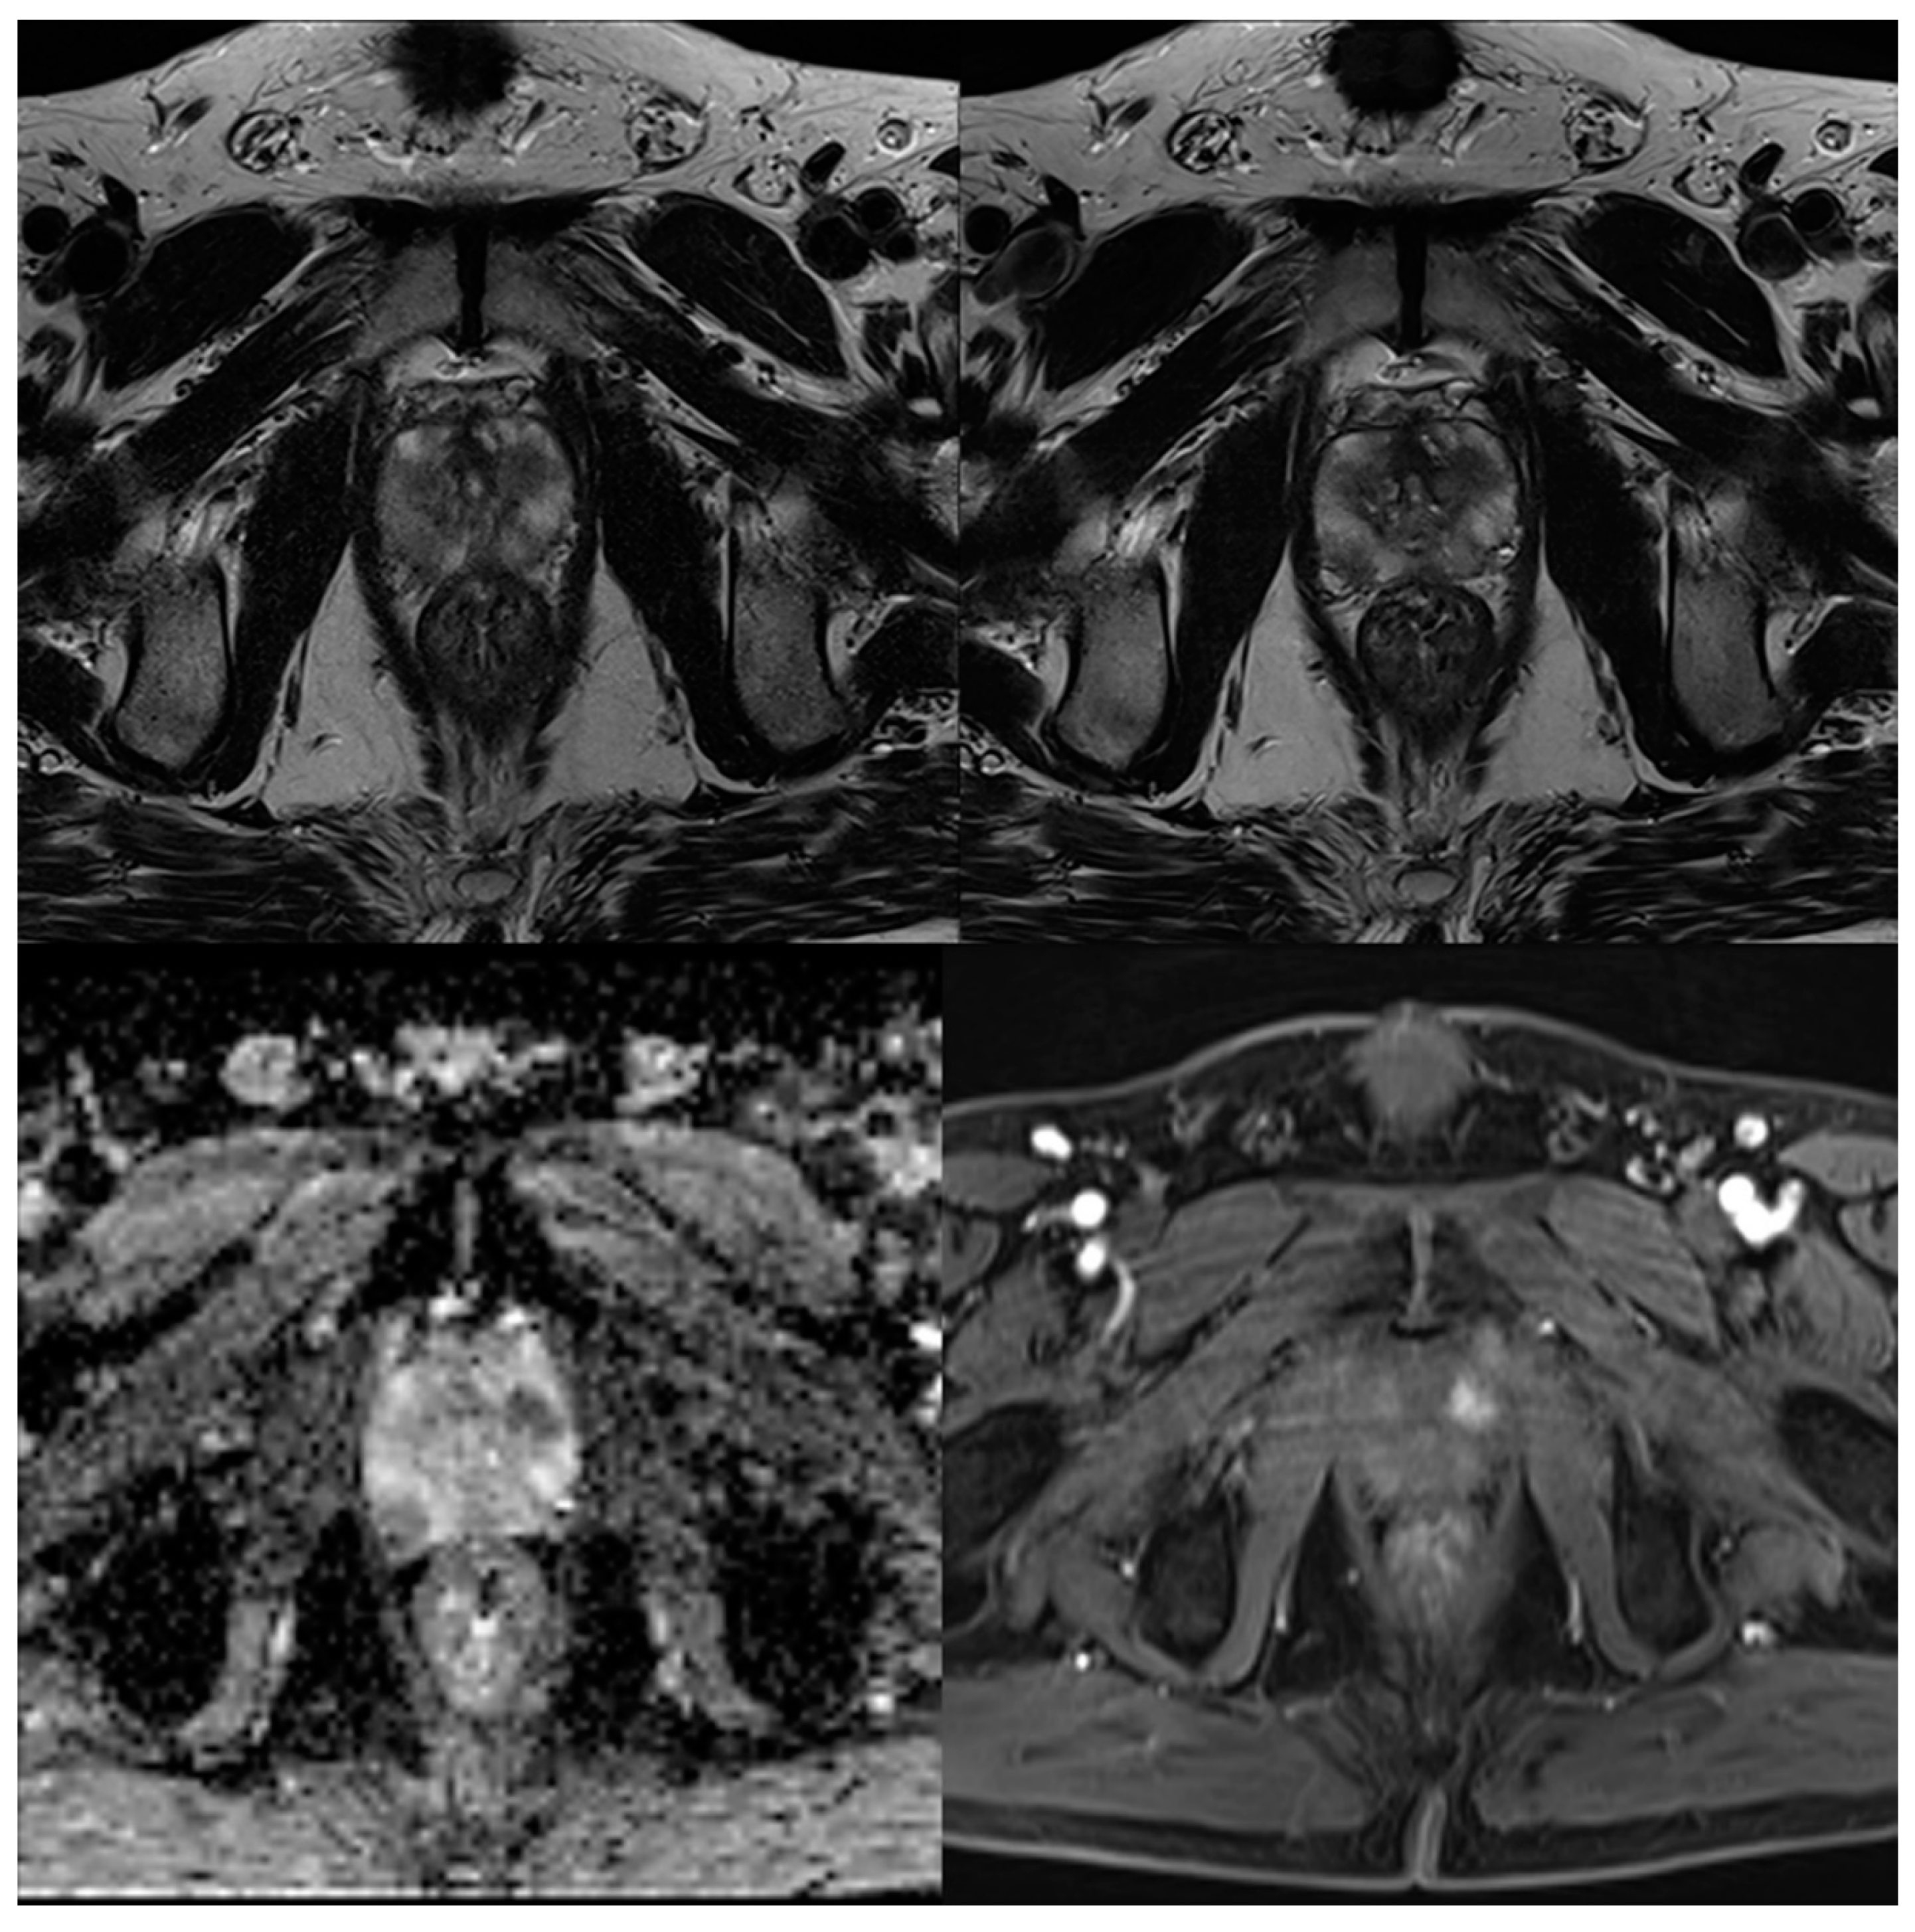

3.2. Evaluation of Qualitative Imaging Parameters

3.3. PI-RADS Scoring and Lesion Conspicuity

| Lesion conspicuity | 3 (3–4) | 4 (4–4) | <0.001 | 3 (3–4) | 4 (4–4) | 0.001 |